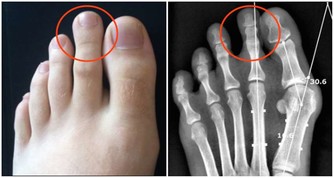

記憶力下降、手腳冰涼、腫脹的腳踝和腿部、靜脈曲張、頭暈、偏頭痛、手腳麻木等。